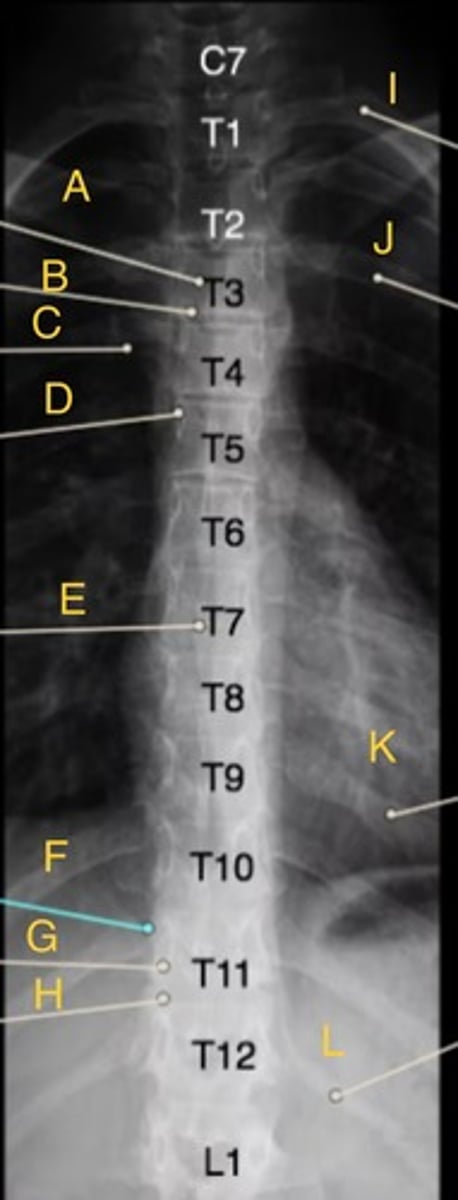

L 1st rib

I.

L 3rd posterior rib

J.

L 9th posterior rib

K

T3 body

A.

T12 floating rib

L

T3-4 intervertebral disk space

B.

T4 transverse process

C.

T5 Pedicle

D.

T7 spinous process

E.

T11 costovertebral joint

F.

T11 inferior articular process

G.

T12 superior articular process

H.